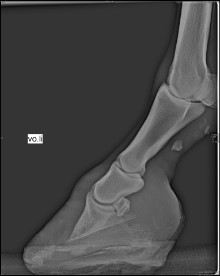

Röntgenbild eines rotierten Hufbeines |